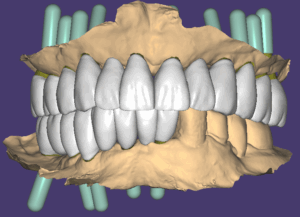

2번째 아래 수술 후 3개월 후에 방문하셔서 스캔바디 스캔을 해서 임플란트 위치를 확인하고 지대주와 지르코니아 보철 디자인을 했습니다.

스캔바디

지대주 디자인이 된 모습